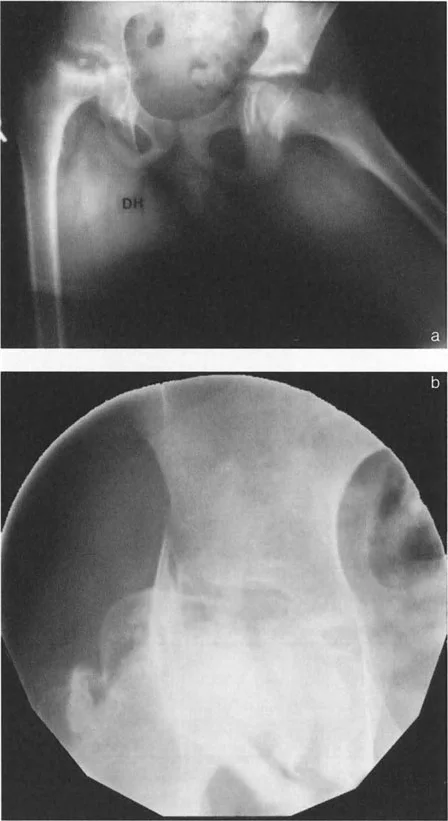

- خلل التنسج النمائي للورك (DDH): يحدث عندما لا يتطور مفصل الورك بشكل صحيح عند الرضع والأطفال، مما يؤدي إلى عدم استقرار المفصل أو خلع جزئي أو كلي.

- انزلاق مشاش رأس الفخذ (SCFE): حالة شائعة تحدث غالبًا في مرحلة المراهقة، حيث ينزلق رأس عظم الفخذ عن عنقه عند صفيحة النمو.

- الأشعة السينية التقليدية: تُظهر صور الأشعة السينية الأمامية الخلفية (AP) والجانبية (Lateral) للورك العظام الرئيسية وتساعد في الكشف عن التشوهات الواضحة.

- التصوير بالرنين المغناطيسي (MRI): يُوفر صورًا تفصيلية للأنسجة الرخوة مثل الأربطة، الأوتار، الغضاريف، ويُساعد في الكشف عن النخر اللاوعائي أو أمراض داخل المفصل.

- الأشعة المقطعية (CT Scan): تُوفر صورًا ثلاثية الأبعاد للعظام، وهي ضرورية لتقييم التشوهات المعقدة والالتواءات وتخطيط الجراحة بدقة فائقة.